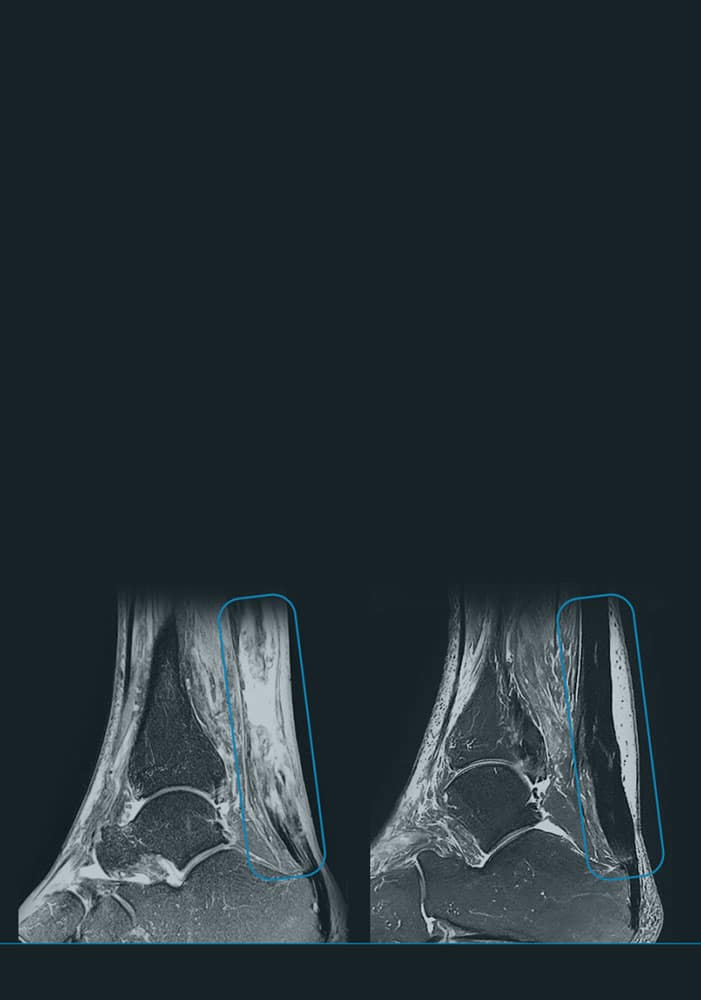

En ITRT hemos demostrado la viabilidad y seguridad de nuestras terapias mediante ensayos clínicos regulados y autorizados por la AEMPS (Agencia Española de Medicamentos y Productos Sanitarios). Una vez superado el ensayo clínico, la AEMPS autoriza el uso del medicamento en pacientes concretos, lo que permite ofrecer tratamientos personalizados con eficacia clínica y capacidad regenerativa demostrada.